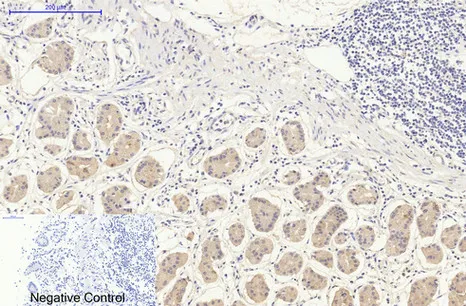

Immunohistochemistry analysis of paraffin-embedded Human stomach tissue using DDIT3 (7G7) antibody.High-pressure and temperature Sodium Citrate pH 6.0 was used for antigen retrieval.Negative control was used by secondary antibody only.